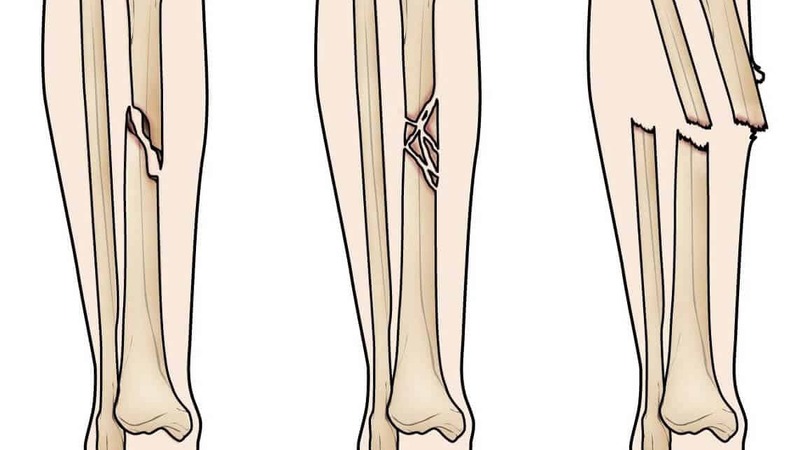

Gãy xương cẳng chân là tình trạng gãy một hoặc cả hai xương cẳng chân, từ mâm chày đến mắt cá chân. Có nhiều cách phân loại kiểu gãy xương cẳng chân, cụ thể: